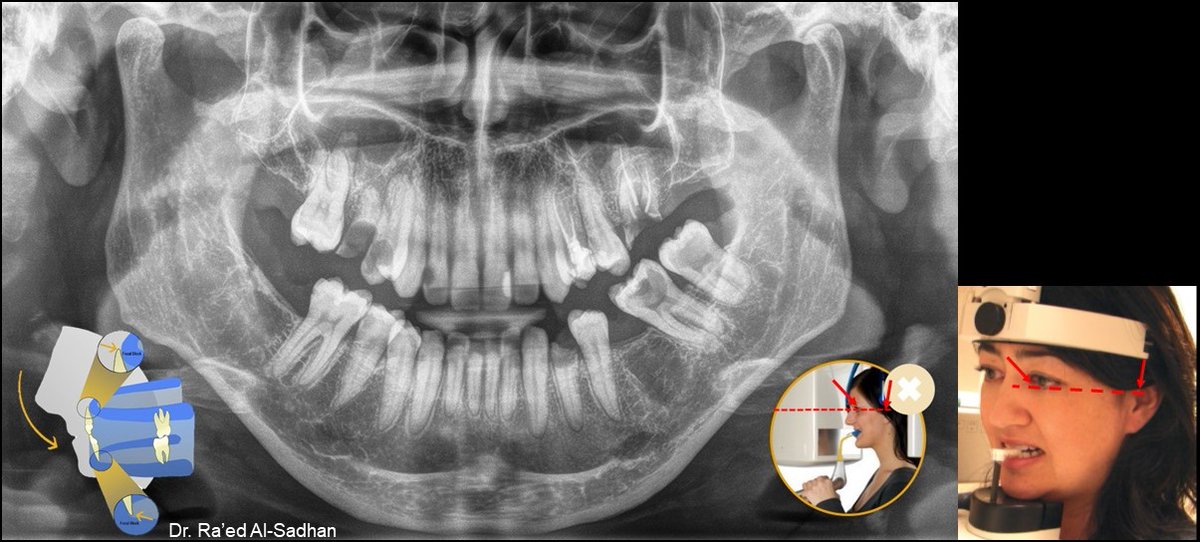

من أكثر التشوهات التي تظهر في صورة الأشعة البانورامية تشوه الصورة نتيجة لعدم ضبط محور فراكنفورت Frankfort plain للرأس مع خط الضوء الأفقي في جهاز الأشعة البانورامية.

الوضع الصحيح للرأس أثناء التصوير البانورامي يضبط فيه طرف الخط الضوئي الأفقي مع محور فرانكفورت Frankfort plain على أعلى فتحة الأذن (upper margin of ear canal (porion ثم رفع أو إنزال ذقن المريض حتى يلامس الطرف الآخر لخط الضوء أسفل محجر العين inferior margin of orbit (orbitale)

وعندما يوضع الرأس في هذا المستوى وتعض أطراف الثنايا على الثلمة التي في العود الذي في جهاز الأشعة incisal pin تكون الأسنان في وسط طبقة التصوير لجهاز الأشعة البانورامية وتظهر صورتها واضحة دون تشوه.

كما ينبغي الانتباه أثناء تصوير الأشعة البانورامية لرفع اللسان ليلامس سقف الفم ليغلق كامل المجرى التنفسي في الفم فلا يتبقى أي هواء في الفم، ولا يكفي فقط رفع طرف اللسان.